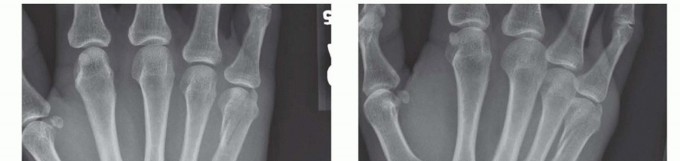

FIG 3 • A. Fracture of the neck of the fifth metacarpal with a flexed, apex dorsal angulation (boxer's fracture). B. Torsional injuries lead to long oblique fractures with a risk for malrotation. C. Short transverse fracture from a direct impact. D. Crush injuries can lead to a combination of injuries with an increased risk of compartment syndrome and significant stiffness. The shortened fourth metacarpal pulls the head of third metacarpal in a proximal and ulnar direction through deep transverse metacarpal ligament. E. Neglected fight bite injury ultimately leading to loss of the metacarpal head. Crush injuries can lead to comminuted fractures with significant soft tissue injuries and a heightened risk of compartment syndrome (FIG 3D).